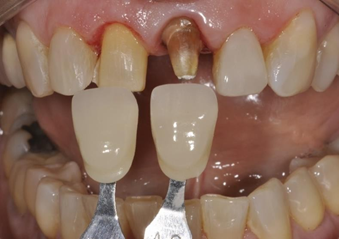

In this particular case, due to the different types of restorations to be fabricated, the correct shade selection is extremely important, as the final shade selection of the restoration must be made, as well as taking the shade of the dentin substrate. With the patient's help, shade A1 from the Vitapan Classical scale (Vita Zanhfabrik GmbH®) was chosen (Figure 7).

Figure 7 Choice of color A1 according to the Vitapan Classical scale (Vita Zanhfabrik GmbH®).

The shade selected for the dental substrate varied between A3.5 and A4 of the same scale. This information was sent to the laboratory in order to select the most appropriate ceramic material for the case (Figure 8).

Figure 8 Substrate color selected between A3.5 and A4 of the Vitapan Classical scale (Vita Zanhfabrik GmbH®).